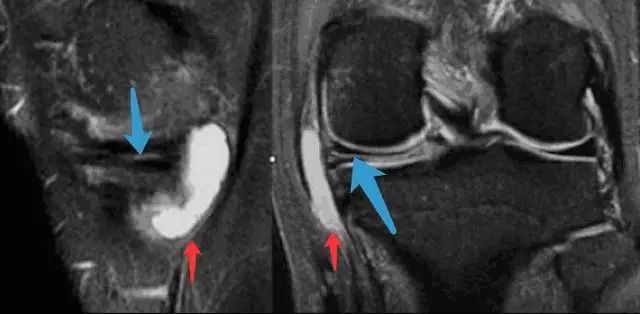

图 13 横行撕裂与半月板囊肿

T2像中可看到明亮的囊肿(红色箭头)和水平走形的线形高信号(蓝色箭头)。半月板囊肿是由于半月板撕裂后组织液聚集在关节腔形成。是否有半月板囊肿对手术入路的选择有重要影响。